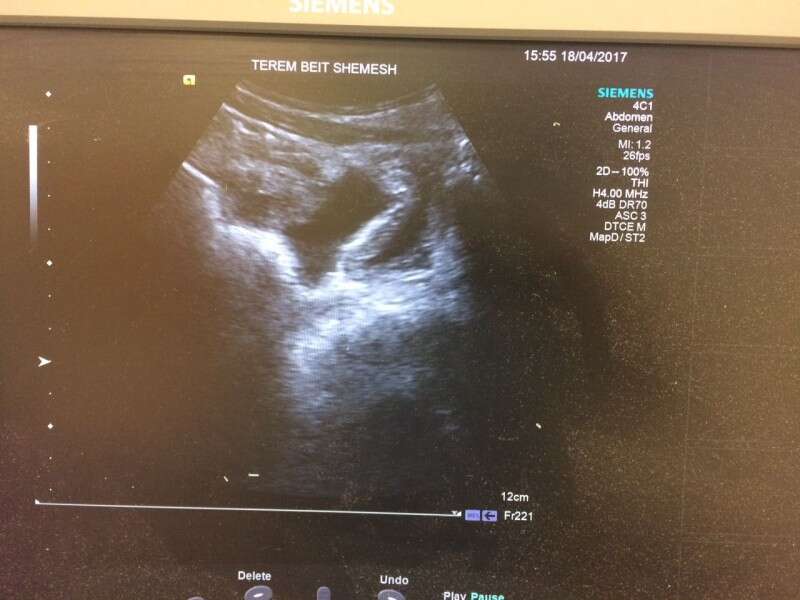

בדיקת האולטרסאונד שחשפה את הקרע בכבד // צילום: דוברות מיון טרם

מאוחר יותר הגיע הילד בליווי הוריו למיון "טרם" בעיר, זאת לאור הכאבים העזים מהם סבל. אנשי הצוות הרפואי בראשות ד"ר זאב ווימפהיימר ביצעו בדיקות מקיפות, בהם בדיקת אולטרה סאונד, במהלכם התגלה דימום פנימי בבטנו של הילד.